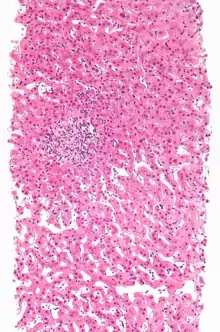

وینیل کلراید یک ماده سرطان زای انسانی در گروه 1 است که باعث افزایش خطر آنژیوسارکوم نادر ، تومورهای مغزی و ریوی و تومورهای بدخیم لنفاوی هماتوپوئیتی می شود. [21] قرار گرفتن در معرض مزمن منجر به اشکال متداول نارسایی تنفسی ( آمفیزم ، فیبروز ریوی ) و سمیت کبدی متمرکز ( هپاتومگالی ، سیروز یا تشمع کبدی ) می شود. قرار گرفتن در معرض مداوم می تواند باعث افسردگی CNS از جمله سرخوشی و گمراهی شود. کاهش میل جنسی مرد ، سقط خود به خودی و نقص مادرزادی از عمده ترین نقایص تولیدمثلی مرتبط با وینیل کلراید است.

سمیت کبدی وینیل کلرید مدتهاست که از دهه 1930 که صنعت PVC در مراحل اولیه بود ، به وجود آمده است. در اولین مطالعه در مورد خطرات وینیل کلراید ، که توسط پتی در سال 1930 منتشر شد ، مشخص شد که قرار گرفتن در معرض حیوانات آزمایش شده فقط با یک دوز بالای کوتاه مدت وینیل کلرید باعث آسیب کبدی می شود. [22] در سال 1949 ، یک نشریه روسی این یافته را کشف کرد که وینیل کلراید باعث آسیب کبدی در بین کارگران می شود. [23] در سال 1954 ، گودریچ اظهار داشت که وینیل کلراید در اثر تماس کوتاه مدت باعث آسیب کبدی می شود. تقریباً هیچ چیزی در مورد تأثیرات طولانی مدت آن شناخته نشده بود. آنها همچنین مطالعات طولانی مدت سم شناسی روی حیوانات را توصیه کردند. این مطالعه نشان داد که اگر یک ماده شیمیایی هزینه آزمایش را توجیه می کند و اثرات سوء آن بر روی کارگران و مردم مشخص است ، نباید این ماده شیمیایی ساخته شود. [24]

در سال 1963 ، تحقیقاتی که بخشی از آن توسط Allied انجام شد ، نشان داد که آسیب کبدی در حیوانات آزمایش شده، از قرار گرفتن در معرض500 ppm کمتر است. [25] همچنین در سال 1963 ، یک محقق رومانی یافته های بیماری کبد را در کارگران وینیل کلراید منتشر کرد. [26] در سال 1968 ، موچلر و کرامر، گزارش دادند که قرار گرفتن در معرض 300 ppm باعث آسیب کبدی در کارگران وینیل کلراید می شود. [27] در یک سخنرانی در سال 1969 که در ژاپن ارائه شد، یک محقق اروپایی که برای صنعت وینیل کلرید در اروپا کار می کند ، اظهار داشت ، "هر مونومر مورد استفاده در تولید VC خطرناک است و تغییرات مختلفی در استخوان و کبد پیدا شد. [28]

در سال 1970 ، ویولا گزارش داد که حیوانات آزمایشی که در معرض 30000 ppm وینیل کلراید قرار دارند ، تومورهای سرطانی ایجاد می کنند. ویولا تحقیقات خود را در جستجوی علت صدمات کبدی و استخوانی در کارگران وینیل کلراید آغاز کرد. یافته های ویولا در سال 1970 برای گودریچ (گودریچ شرکت هوافضای آمریکایی است، که در تولید انواع تایر، لاستیک، تجهیزات الکترونیکی، قطعات هواگرد و فناوری هوافضا فعالیت مینماید)و صنعت "پرچم سرخی" بود. [29] در سال 1972 ، مالتونی ، یکی دیگر از محققان ایتالیایی صنعت وینیل کلرید در اروپا ، تومورهای کبدی (از جمله آنژیوسارکوم) را در اثر مواجهه با وینیل کلرید به میزان 250 ppm به مدت چهار ساعت در روز یافت. [30]